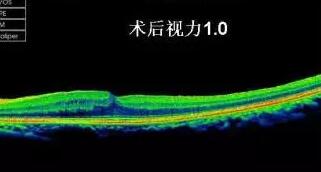

黄斑前膜